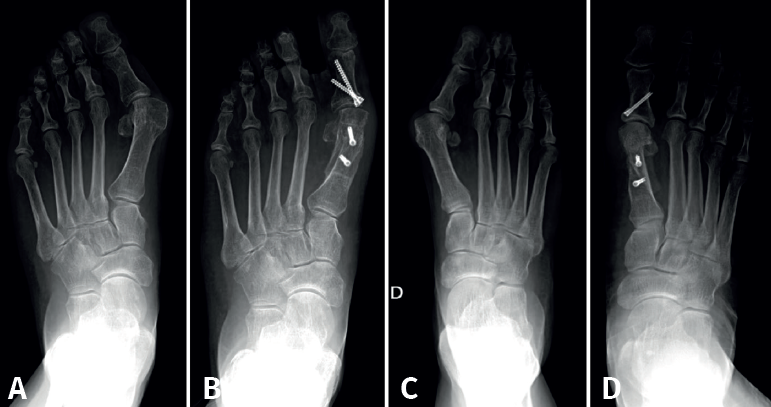

Entre todas las técnicas quirúrgicas que se emplean para el tratamiento destaca la osteotomía de Scarf, debido a que es una técnica muy versátil a la hora de abordar el tratamiento quirúrgico del HV en sus diferentes grados de deformidad(6). Esta técnica quirúrgica, descrita inicialmente por Meyer a principios del siglo XX y popularizada posteriormente por Samuel Barouk junto con Lowell Weil(7), consiste en la realización de un corte longitudinal largo y 2 cortes transversales en sus extremos. Los ángulos y direcciones de estos se modificarán en función de la acción principal que se quiera realizar: acortar, alargar, desrotar, descender, etc. Con el tiempo, la técnica inicial descrita por S. Barouk ha sido modificada para optimizar la corrección, la estabilidad y las posibles complicaciones de la cirugía(8).

Esta técnica suele ser complementada con una osteotomía de falange proximal del primer dedo (Akin) para corregir la rotación del primer dedo. Algunos ejemplos de pacientes intervenidos en nuestro centro se recogen en la Figura 3.